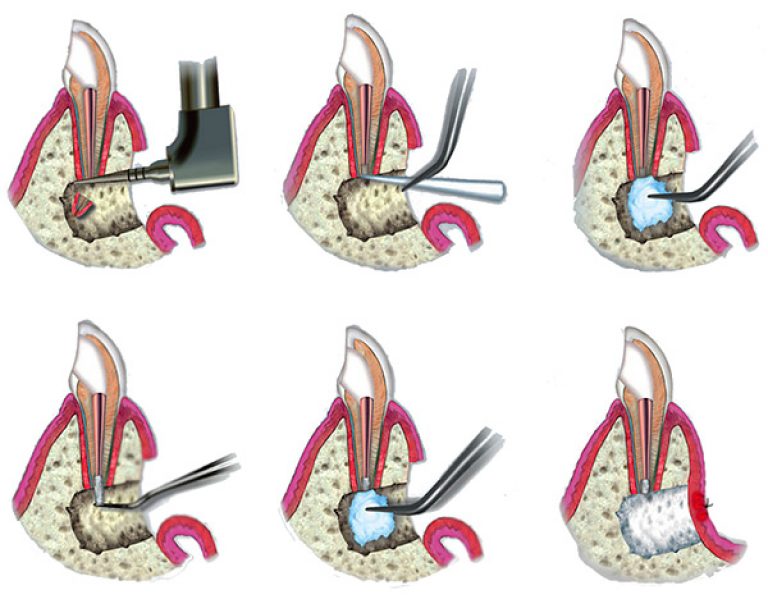

Реплантация зуба: Этапы и особенности операции